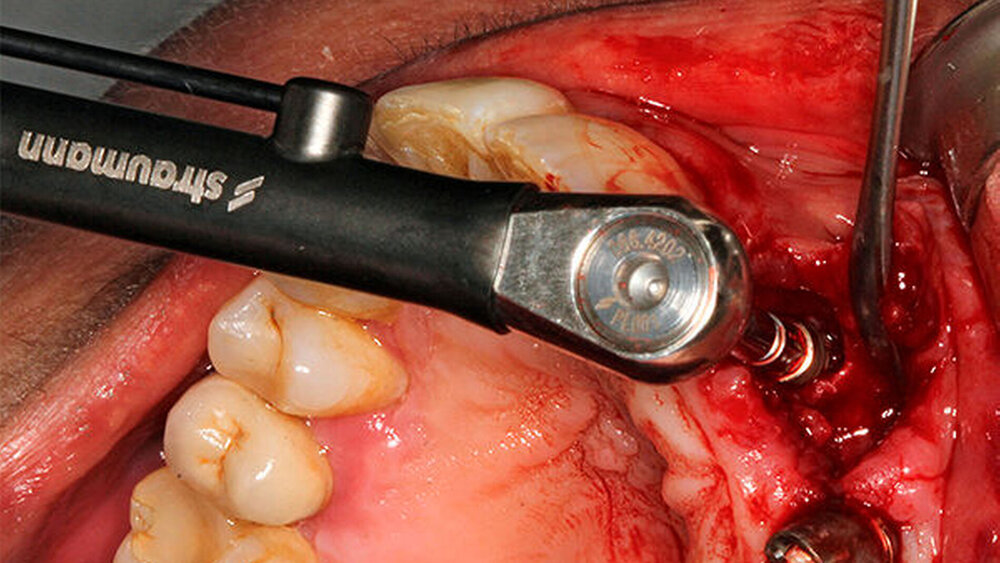

Schnutenhaus:

Ostell dient vor allem der Dokumentation; das Gefühl, wie das Implantat eingebracht ist, halte ich aber für maßgeblicher. Ich messe deshalb über die Ratsche, mache die letzten Drehungen also manuell.